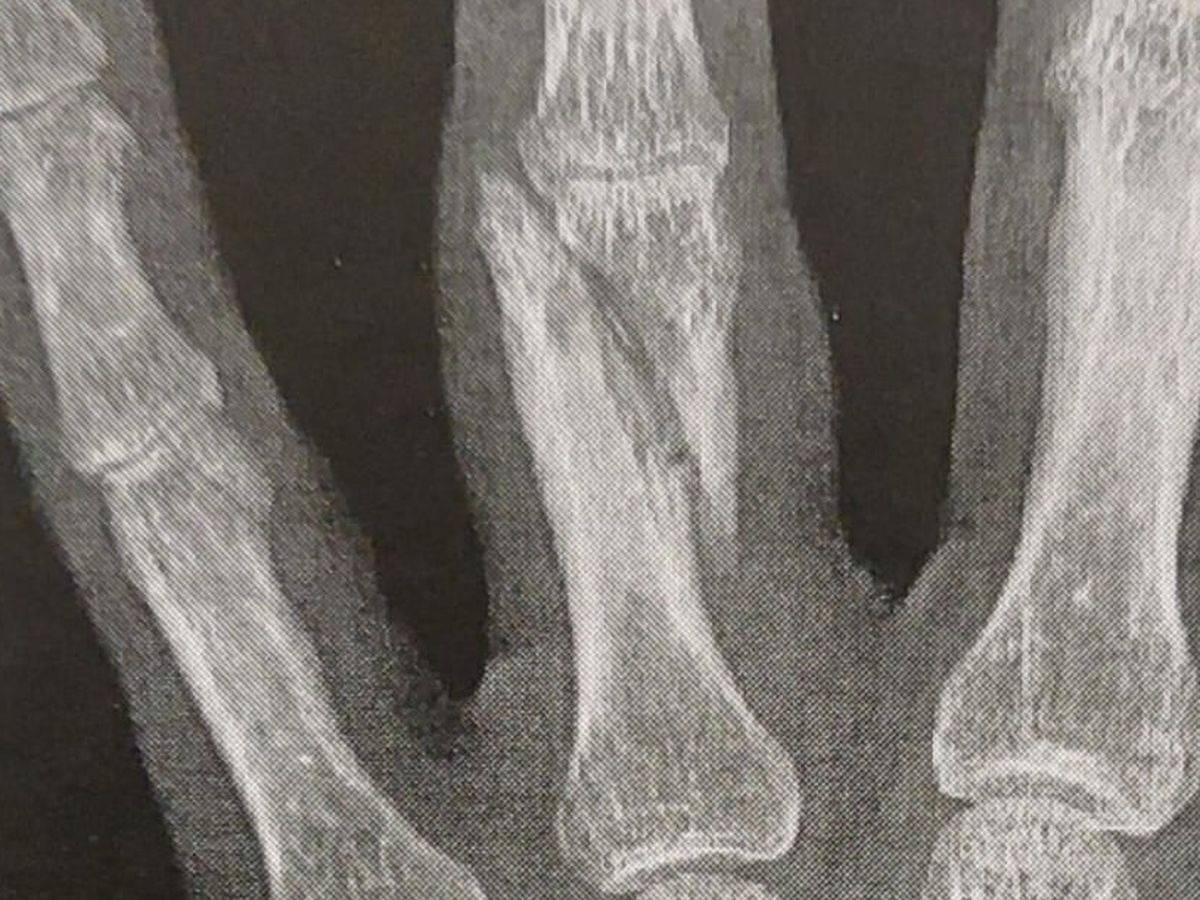

Il y a quelques jours, notre cher ami Jameel se faisait agresser violemment dans la rue pour ses positions politiques. C’est la 2e fois en un mois qu’il subit une agression raciste… Il a une double fracture à la main cette fois-ci, et il doit donc se faire opérer.